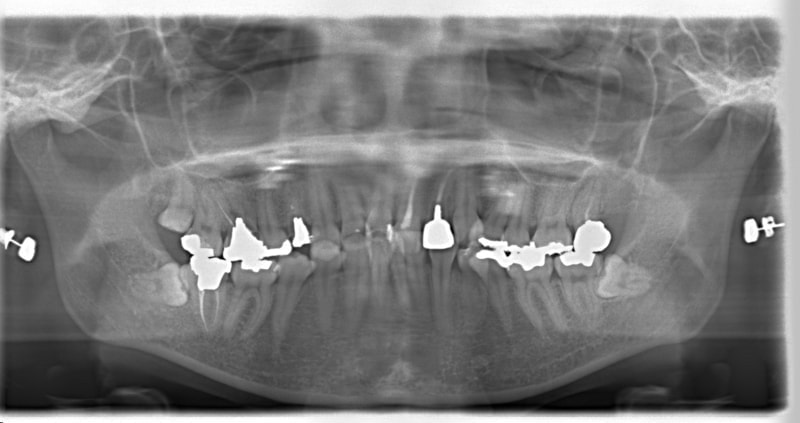

右下7番欠如歯(保存不可能歯につき抜歯)右下8番利用

治療法:フルパッシブブラケット:クリアスナップ

治療後(3年2ヶ月後)